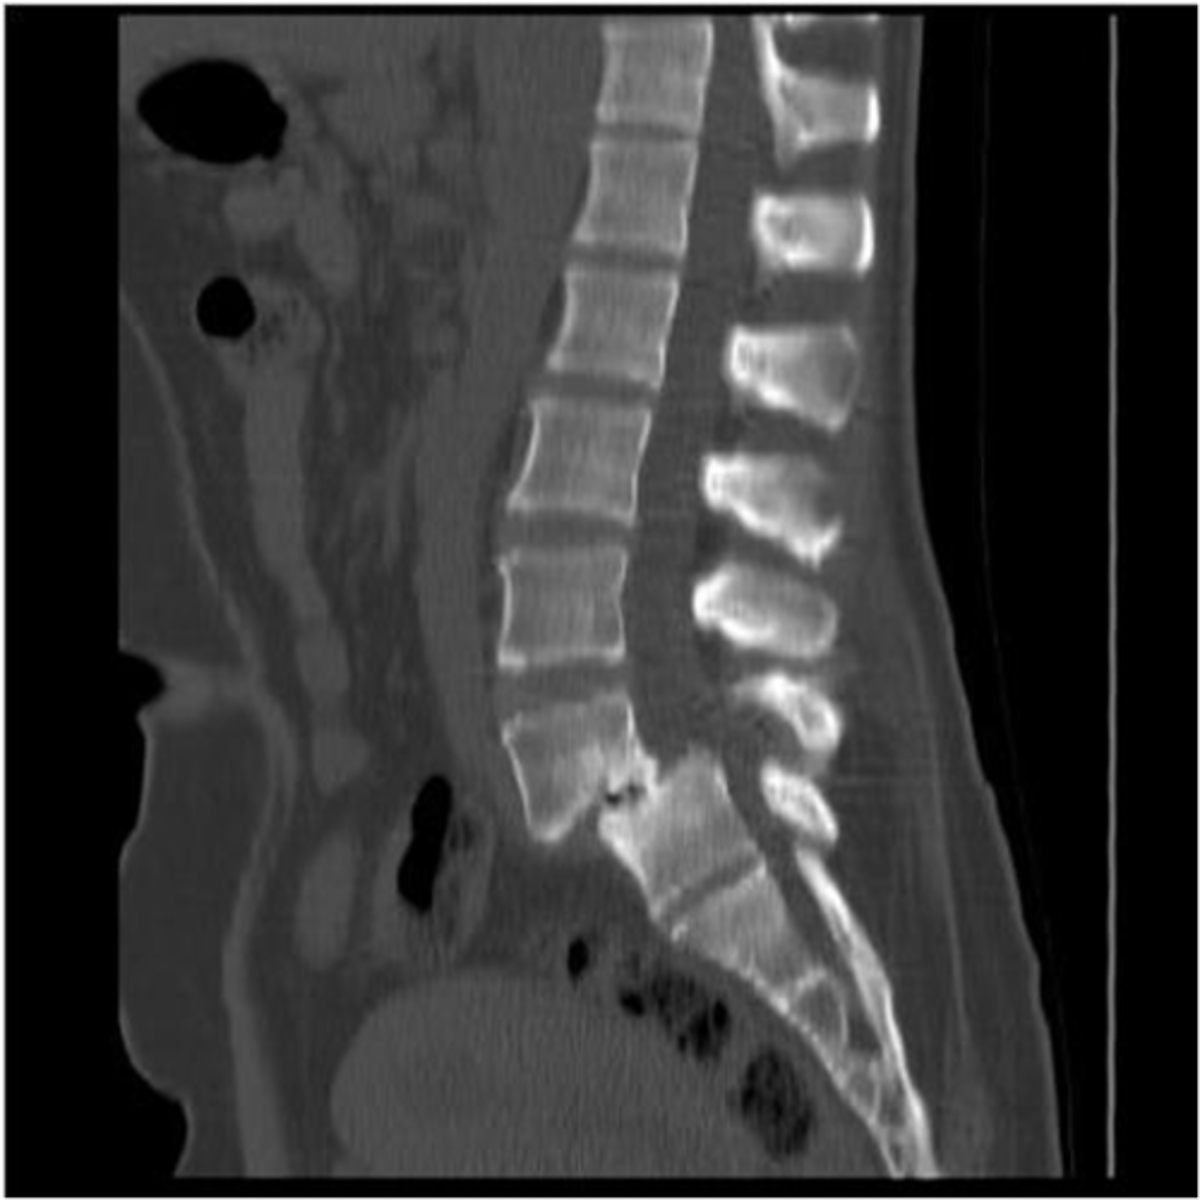

spinal stenosis

Narrowing of the spinal canal that causes pressure on the spinal cord (nerves)

spinal stenosis etiology

osteophytes, disc herniation, tumors, trauma

what are the s/s of spinal stenosis

mild-severe pain, paresthesia, and muscle weakness

cauda equina syndrome is a form of _____ where all nerves in the lower spine are compressed

s/s of cauda equina syndrome

low back pain, radiculopathy, lower extremity weakness, reduced, incontinence of bowel/bladder